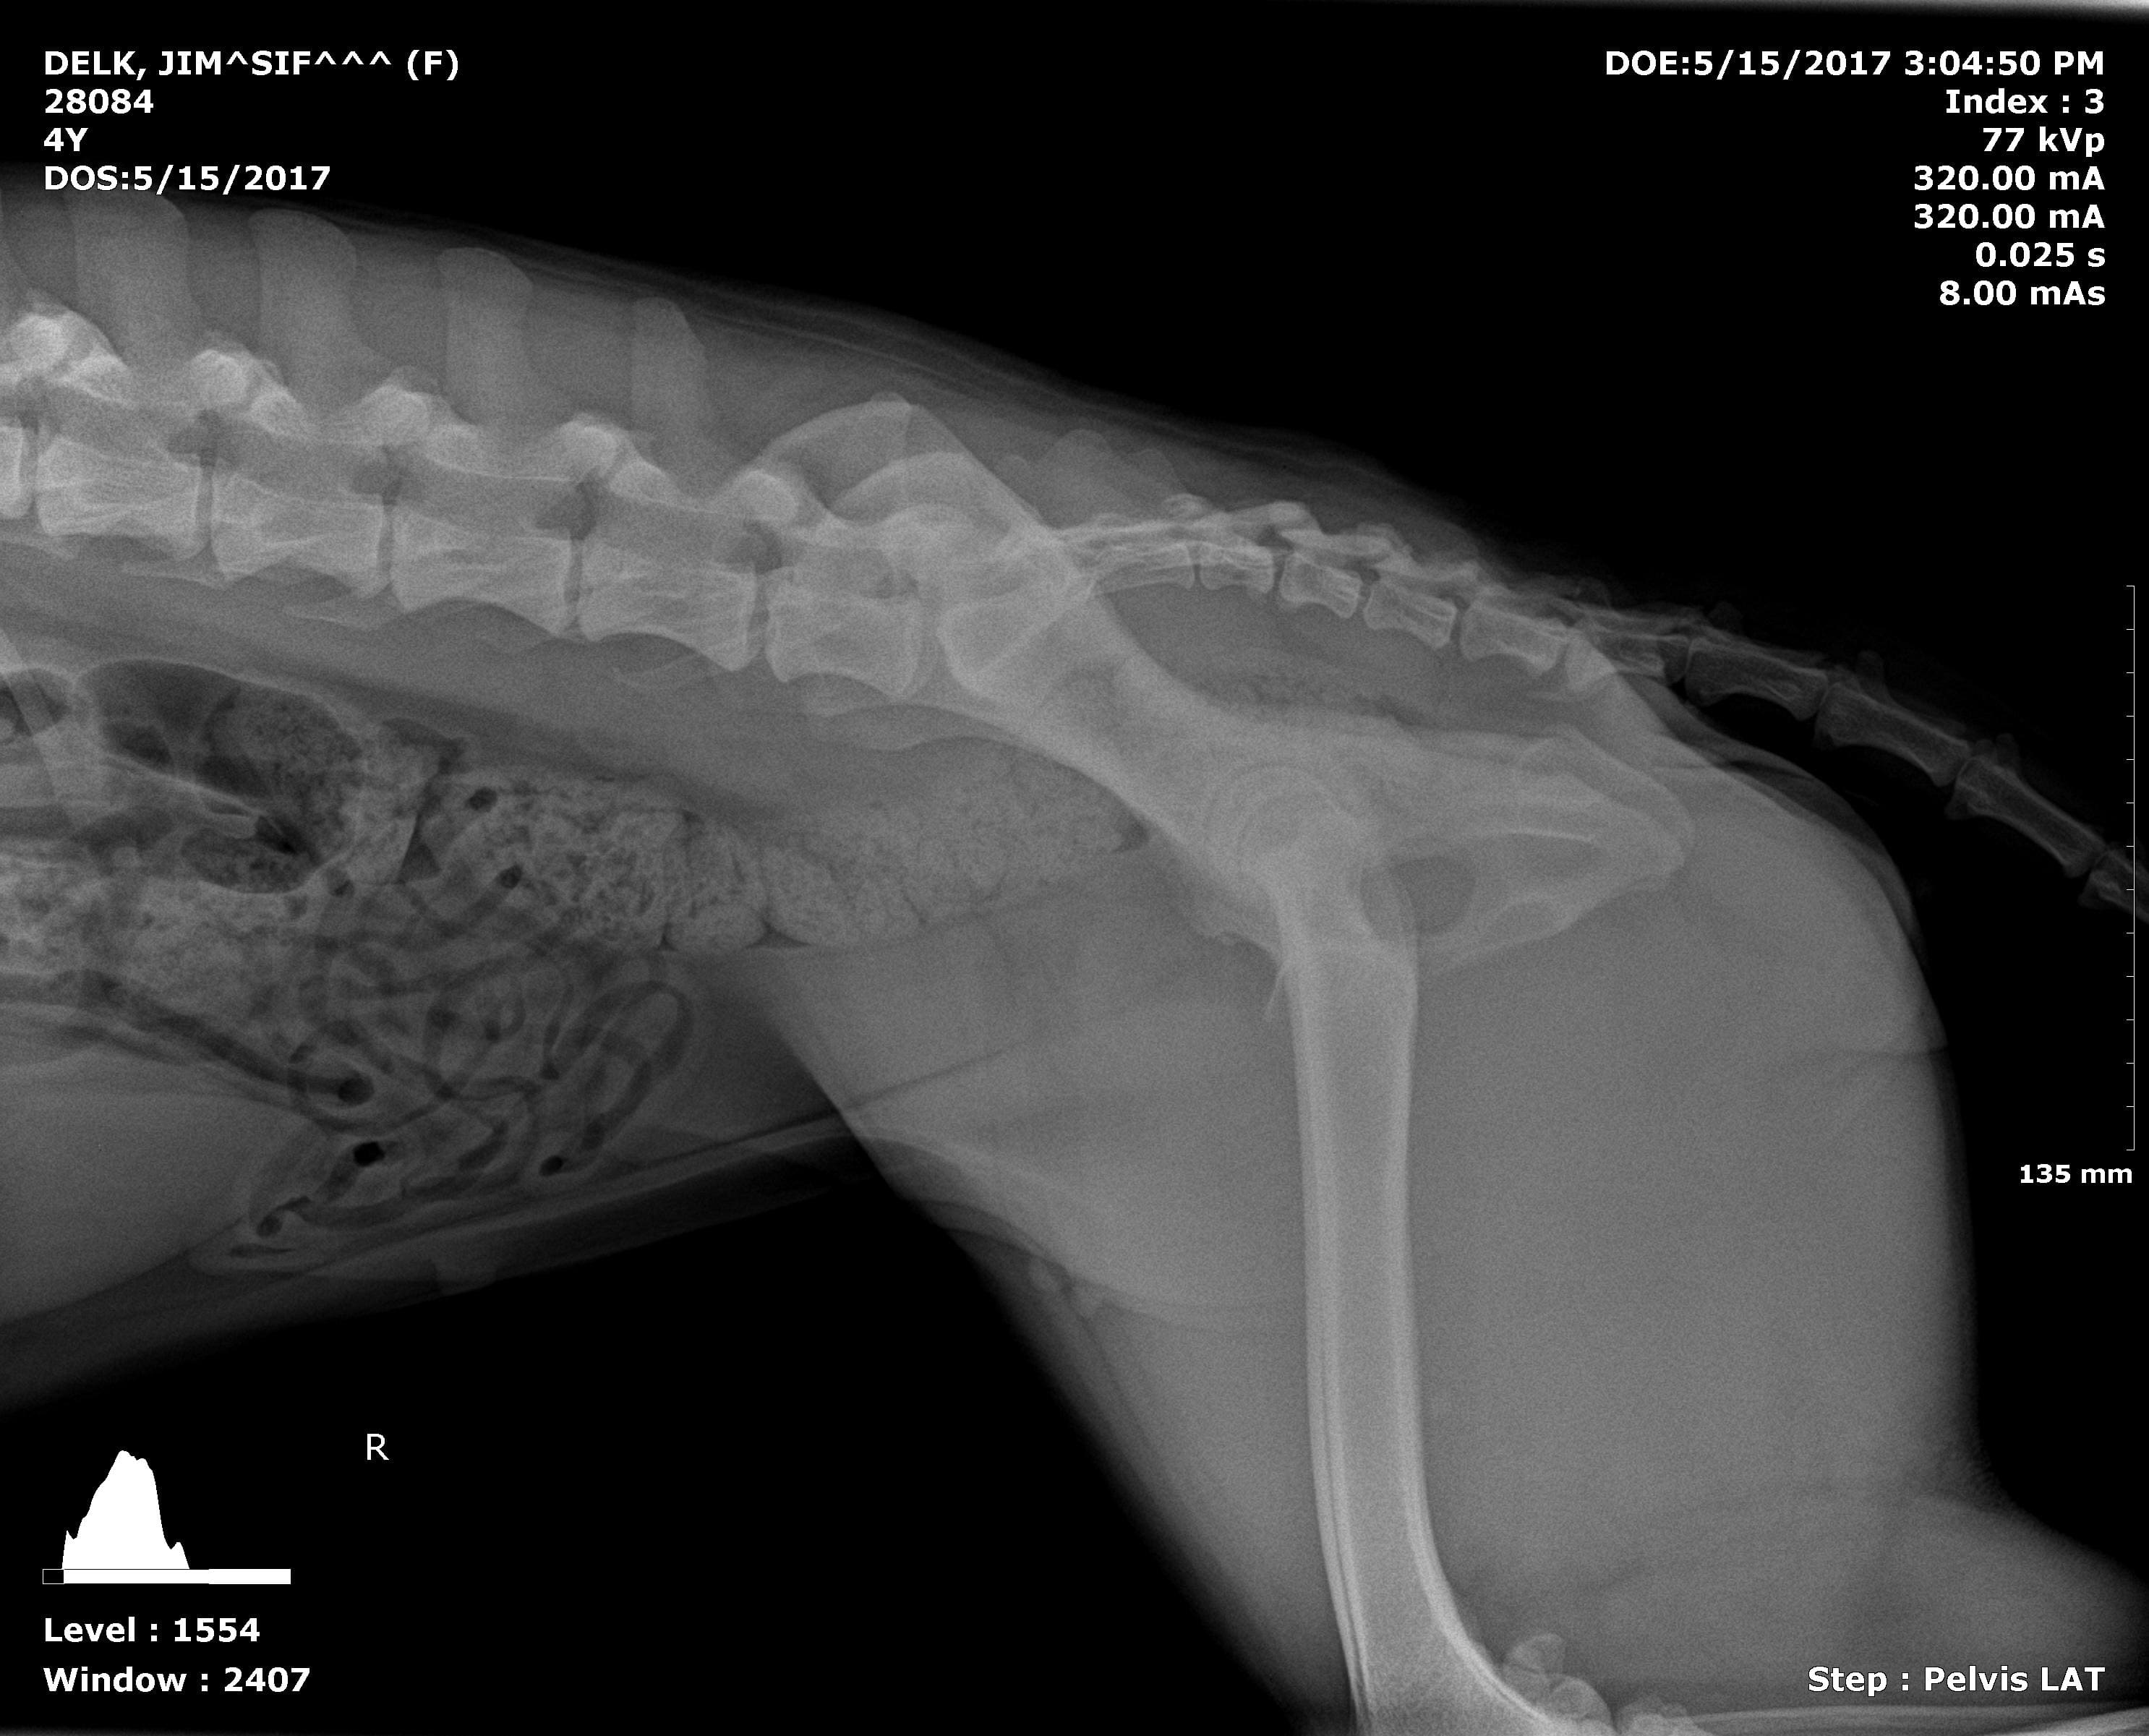

My dog doesn't have full function of her back right leg and will not correct it if it is moved out of place. We were referred to LSU for an MRI. Is there any other issues that she could have other than degenerative myelopathy? We are so scared we are going to lose our baby. She is a German Shepherd, six years old.

While degenerative myelopathy is a concern giving your dogs breed and these clinical signs there are other possible causes. The MRI could help show if there could be an infection affecting the spinal cord, or herniated disc, or even some sort of mass that could be potential be removed. While none of those sound like good alternatives some of them may be curable or even manageable longer than to degenerative myelopathy.